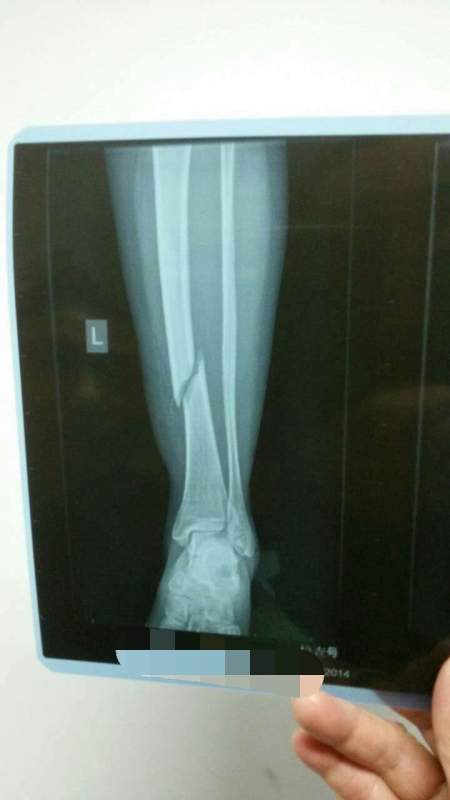

ÂèÂè¹ÇÕÛÁË£¬¹ÇÓúºÏЧ¹ûÒ»Ö±²»ºÃ£¬ÇóÖú ÒÑÓÐ9È˲ÎÓë